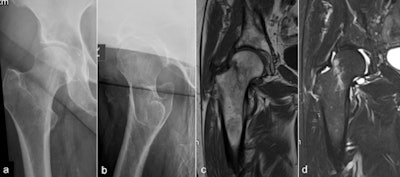

Plain x-ray versus MRI

The majority of femoral neck fractures are readily diagnosed on dedicated plain radiographs, but around 3% to 4% of hip fractures can be occult, resulting in a delayed diagnosis that can significantly increase morbidity and mortality, according to according to a literature search by Wong and colleagues (source: Scientific World Journal, 2013;2013:830319. World Journal of Emergency Surgery, 2015, vol. 10:1, pp. 55. Arch Orthop Trauma Surg., July 2010, Vol. 130:7, pp. 915-920).

The National Institute for Health and Care Excellence (NICE), an independent public body that provides guidance in England, recommends MRI in cases of suspected occult hip fracture within 24 hours, if dedicated radiographs are negative, they explained.